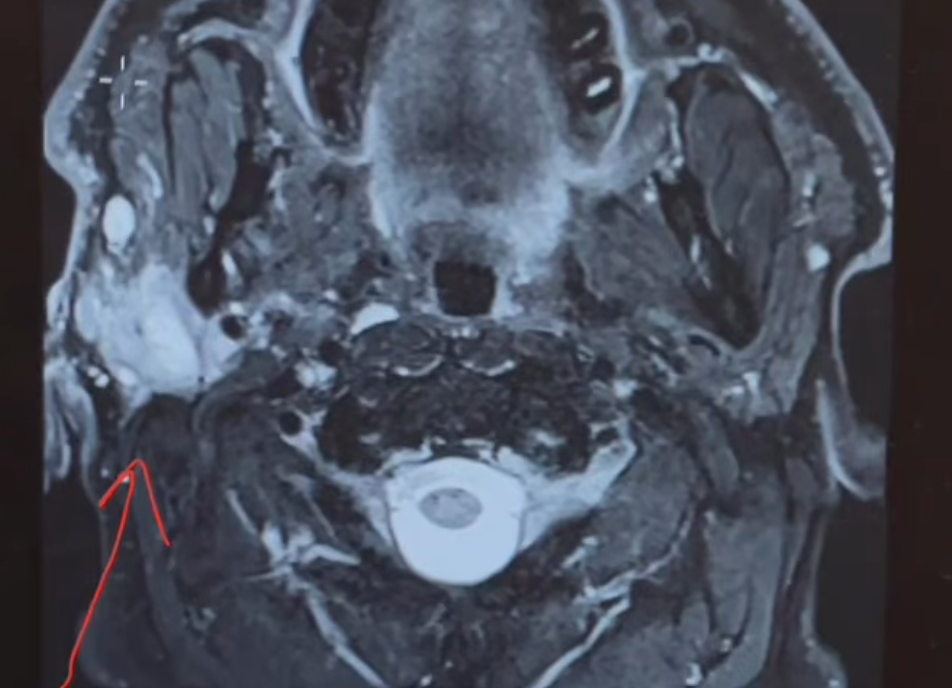

They continued booking specialist appointments on the road as they traversed the state, including a biopsy and a CT scan.

The diagnosis was grim: a stage 4 salivary duct carcinoma.

Jones needed radical surgery to remove the tumour, which has impacted his vision and facial nerves, and will now undergo radiotherapy treatment.